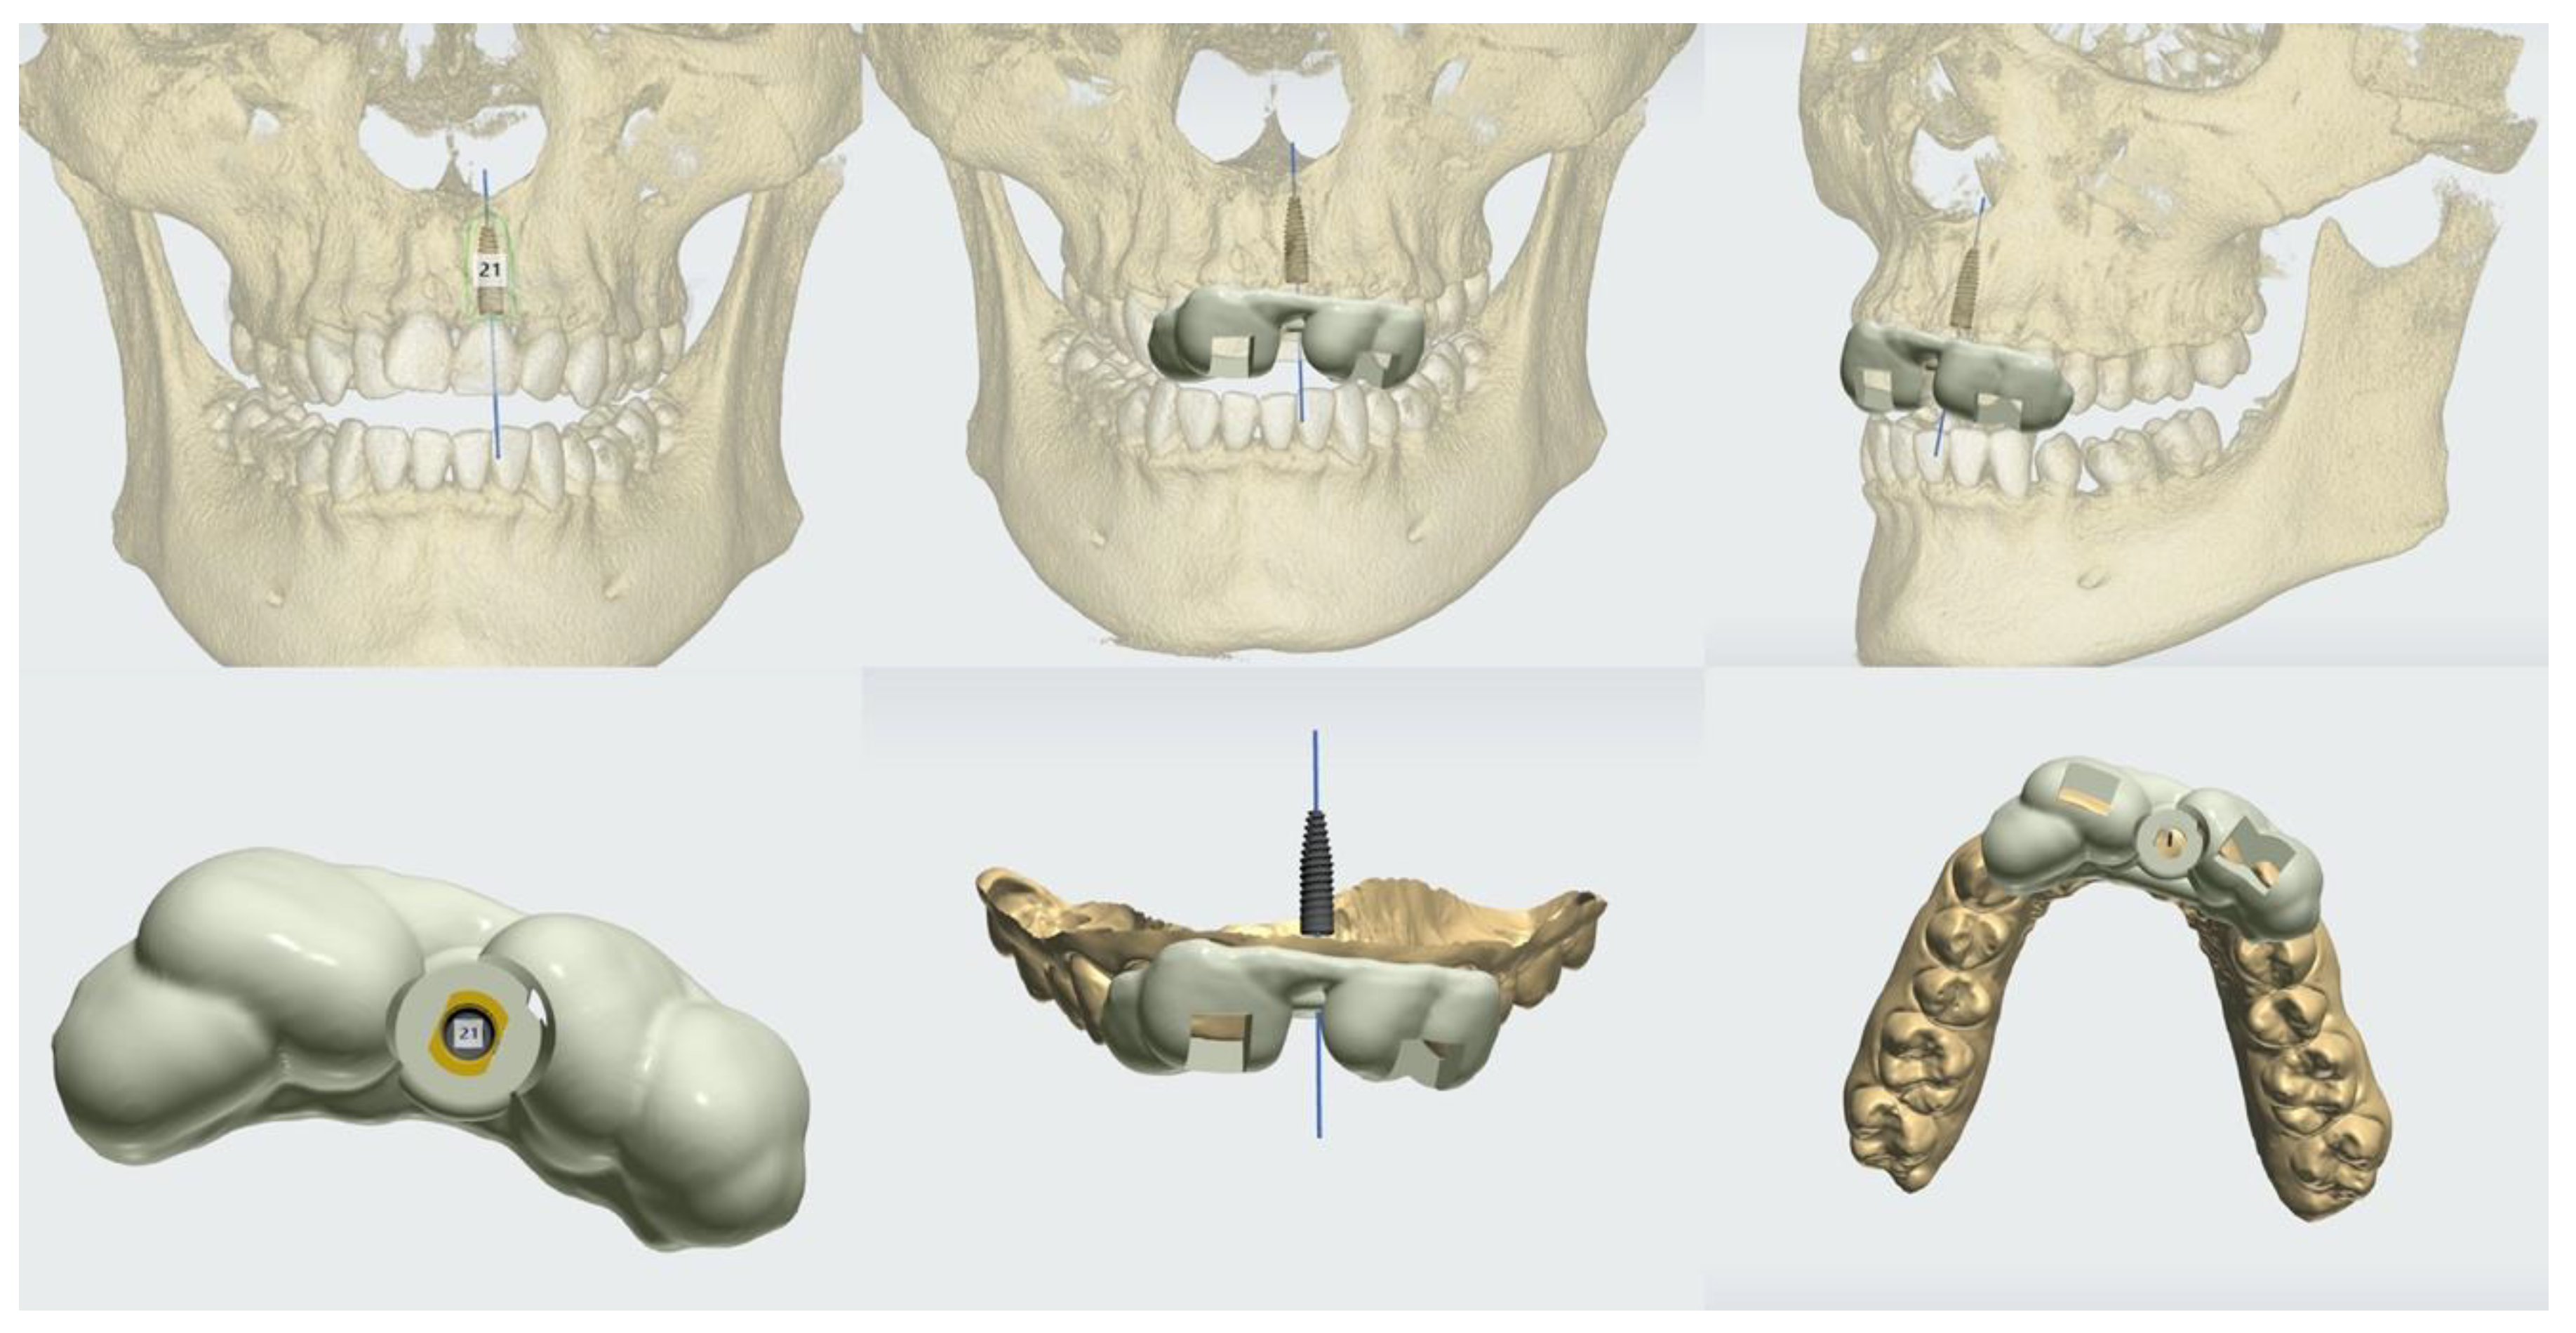

3.1. Case No. 1

- The extraction of tooth 21, followed by orthodontic treatment with aligners and guided implant surgery of tooth 21 at the beginning of the orthodontic treatment.

- A horizontal attachment was added onto the temporary crown of tooth 21 for distalization using the implant as skeletal anchorage.